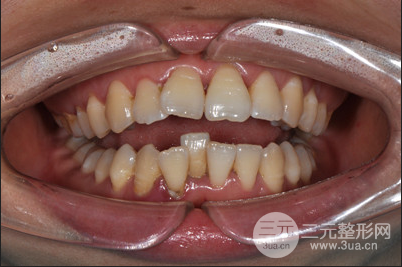

牙齒矯正時間真的太漫長了,在15年做的牙齒矯正,當(dāng)時還是找的黎主任做的面診和整個較真過程,一直以來牙齒很不整齊,關(guān)鍵是還有凸嘴的困擾,在面診之后才知道原來是上下牙列擁擠、上下頜牙弓狹窄、雙頜前突,做牙齒矯正是在所難免的了。

對一次緩解拔了四顆智齒,太專業(yè)的緩解矯正過程我也說不上來,只知道為了減輕牙齒之間的擁擠程度,不得不拔牙,其實我的凸嘴不算特別嚴(yán)重,在拔牙之后做矯正固定就可以了,但是既然選擇了做整形就要做到很好的果,所以在醫(yī)生的專業(yè)保障下做了牙齒正畸,開始了我的漫長牙套之路。